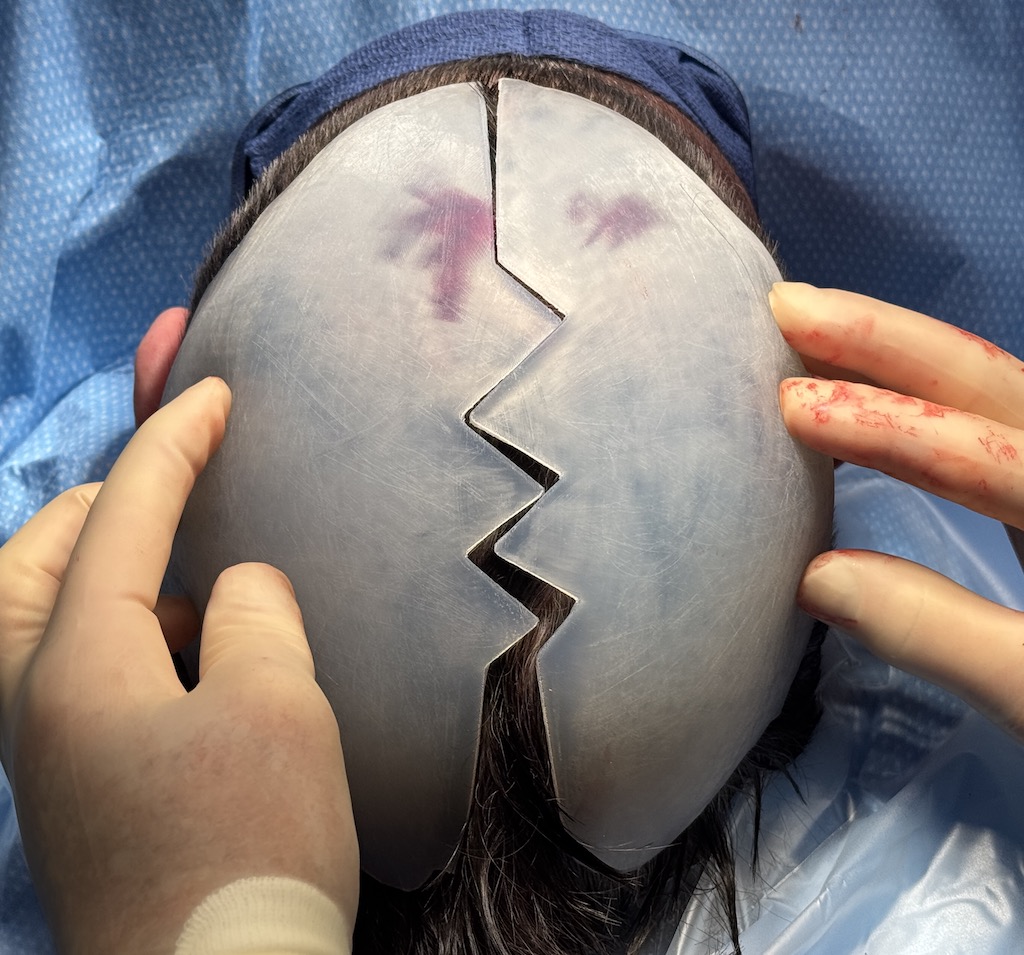

Desire for major head reshaping with a taler and wider head shape.

Placement of large two piece custom skull implant through a sagittal scalp incision.